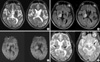

A 39-yr-old man visited the emergency department with a 7-day history of hypesthesia of the left face and extremity and ataxia. He had a history of memory disturbance, disorientation, and general weakness after tooth extraction at 6 yr ago. At that time he had recurrent oral ulcers and iritis. Pathergy skin tests were negative. Physical examination revealed multiple cutaneous lesions both legs, which were confirmed by biopsy as erythema nodosum. Brain magnetic resonance imaging (MRI) showed high signal lesions on both thalami (Fig. 1D). He was diagnosed with Behçet's disease, particularly NBD, according to the criteria of the International Study Group of Behçet's disease (6). Previously, he had been treated with a high dose of intravenous methylprednisolone, and his symptoms had improved prior to this presentation.

Blood cell count, renal and liver function tests, and electrolytes were within normal limits. Erythrocyte sedimentation rate was 7 mm/hr, and C-reactive protein 0.2 mg/dL. HLA-B51 was negative. Pathergy skin tests were negative. Cerebrospinal fluid (CSF) examination showed clear color, slight high pressure (180 mmH2O), lymphocytic pleocytosis (25/µL), and normal protein and glucose levels. CSF immunoglobulin G slightly increased (4.69 mg/dL; normal range 0.00-4.00 mg/dL) and Ig G index was 0.562 (normal range 0.00-0.77). CSF culture was sterile and tests for herpes simplex, varicella zoster, epstein-barr, Japanese encephalitis virus were negative. T2-weighted MR images and fluid attenuated inversion recovery (FLAIR) images showed high signals in the right thalamus, and diffusion-weighted images showed slightly high signals in the same areas. MR angiography was normal. Previous lesions on the left thalamus disappeared (Fig. 1A-C).